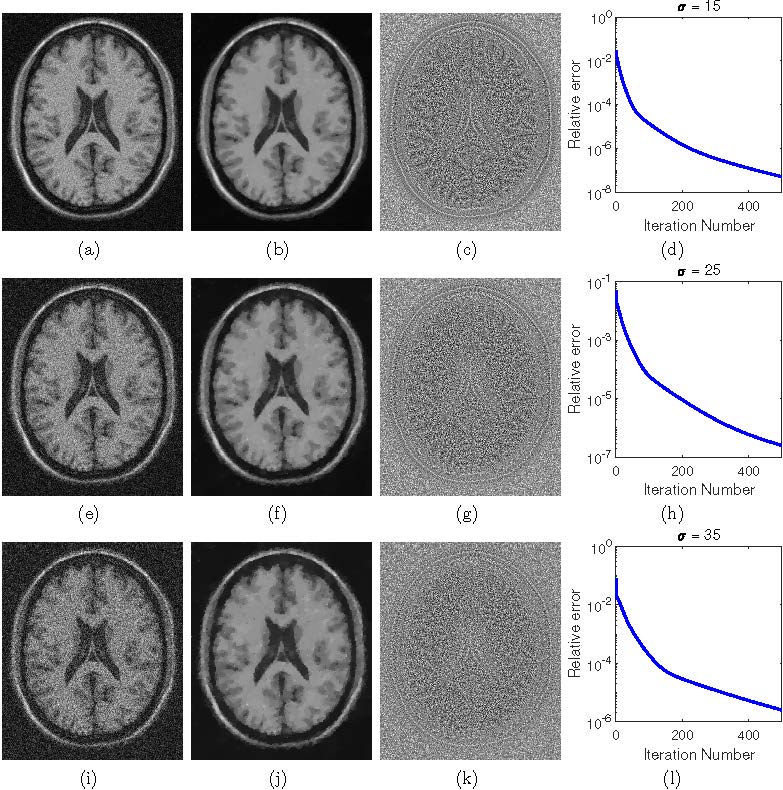

磁共振成像在医学图像处理中有着广泛的应用。含噪声的磁共振数据通常建模为Rician分布。因此,通常把从含噪声的磁共振图像中估计出干净图像的过程称为Rician噪声去除。由于Rician噪声对信号的依赖性,直接提取干净图像具有很大的挑战。该文提出了一种新的变分方法来去除磁共振成像中的Rician噪声。该文首先探讨复值图像(complex images)的高斯噪声去除和幅度图像(magnitude images)的Rician噪声去除之间的联系,然后通过信噪分离建立约束优化模型。该文中的模型不同于以往的基于最大后验概率的模型,后者使用Rician分布概率密度函数建模,不可避免地包含复杂的贝塞尔函数,导致模型求解时需要很高的计算成本。该文采用能保证收敛的交替乘子方向法求解所提出的球面约束优化模型。与现有变分方法的数值比较表明,该文方法在图像恢复质量方面效果相当,但平均节省了约50%的总计算成本。